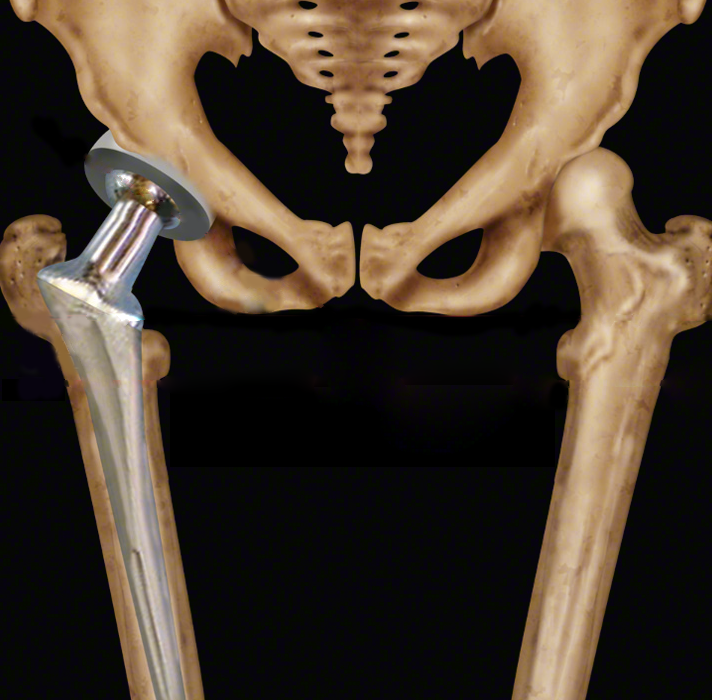

Protez cerrahisi sırasında çıkarılan femur başında eklem kıkırdağı harabiyeti görülüyor.

Total Kalça Artroplastisi: İlerlemiş kalça kireçlenmelerinde genellikle kalça protezi takılır. Protez ameliyatı için hastalığın sadece ileri derecede olması yetmez. Hastanın şikayetleri de ameliyat kararını desteklemelidir. Ağrı ve hareket kısıtlılığı hastanın hayat kalitesini düşürmüşse, gece ağrısı varsa, ağrı ilaçlarla geçmiyorsa ve hastanın yürüme mesafesi kısalmışsa protez ameliyatı düşünülür. Ameliyat sonrasında hastaların erken mobilize olabilmesi ve kısa zamanda günlük aktivitelerine dönebilmesi bu yöntemin avantajlarıdır.